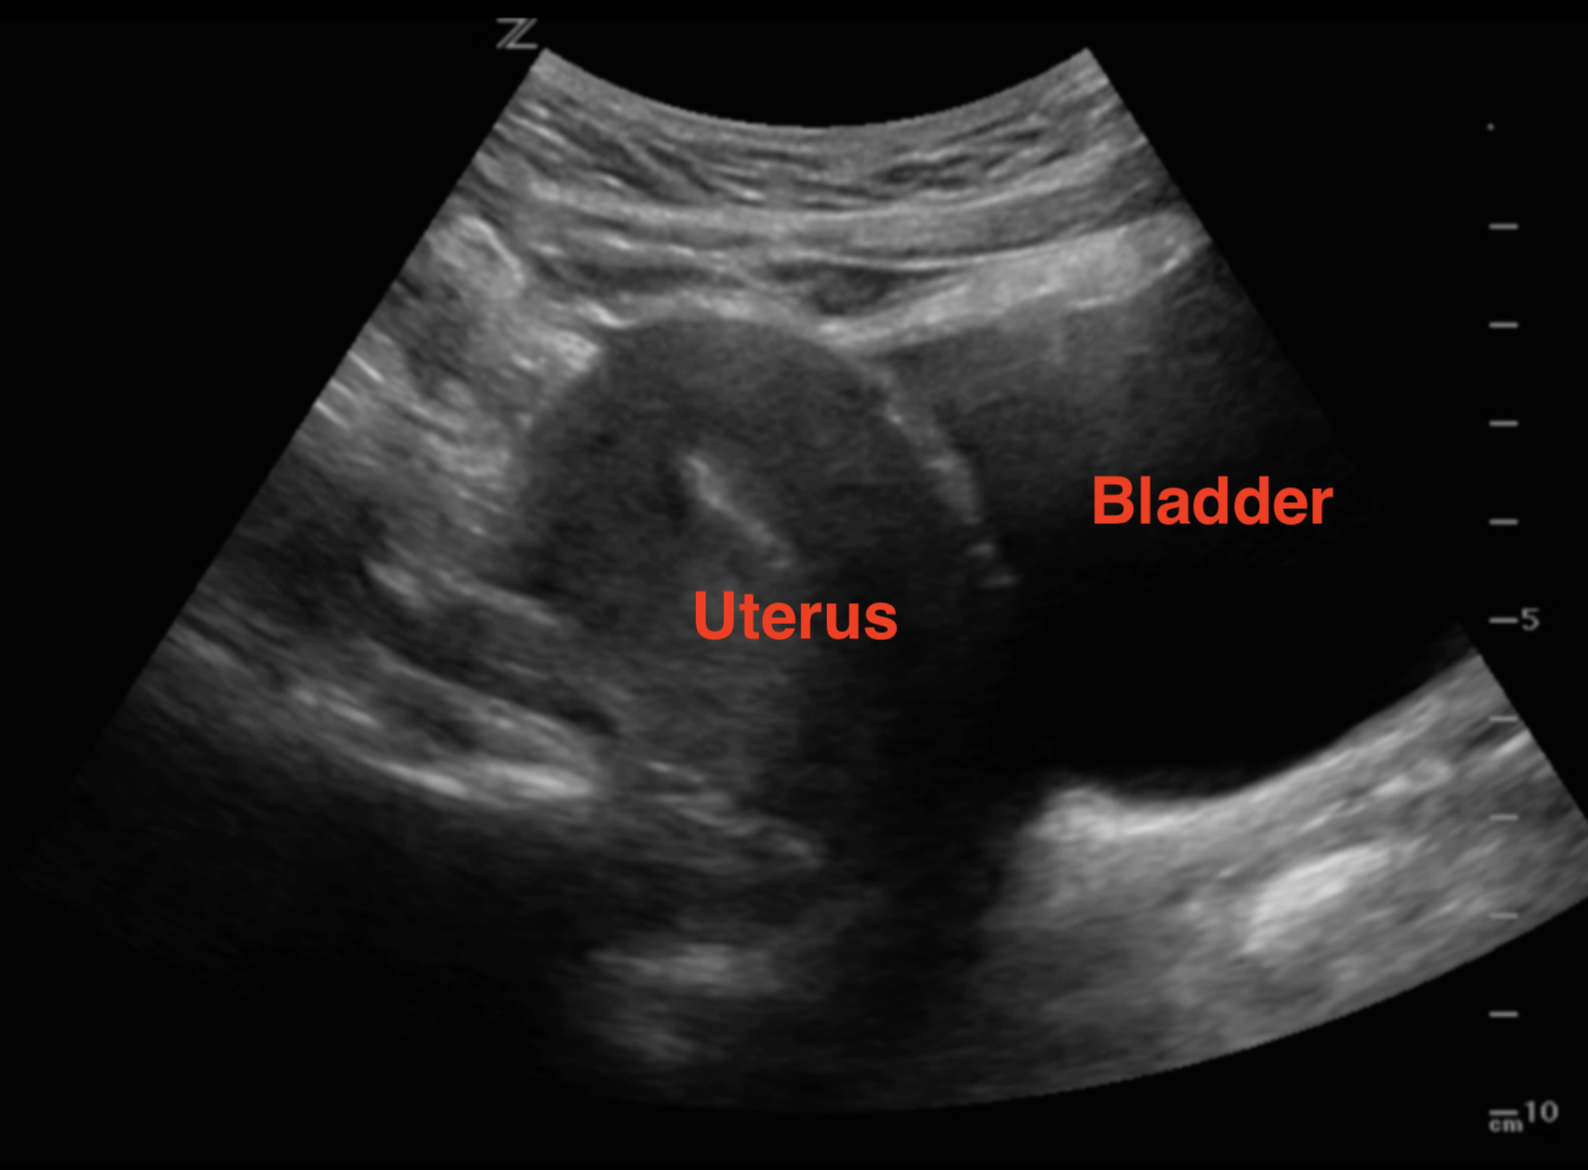

YouTube Ultrasound Ultrasound Sonography Sonography

Endometrial Thickness Ultrasound Image Appearances Endometrium

Uterus Ultrasound Normal Vs Intramural Fibroid Images Uterine

Sagittal Uterus Ultrasound

UTERINE ULTRASOUND IMAGING